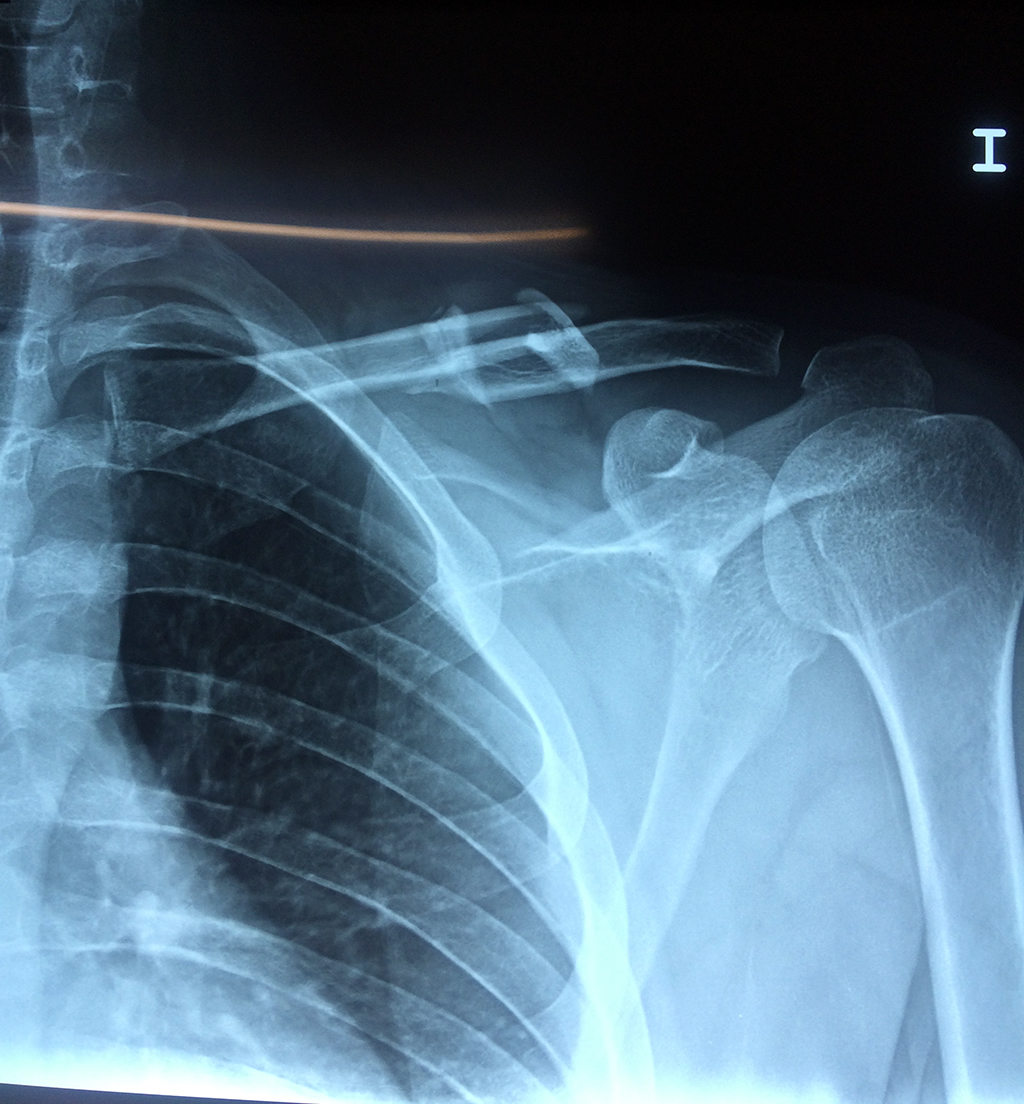

Clavícula

La clavícula es un hueso largo, con forma de "S" itálica, situado en la parte anterosuperior del tórax. Junto con la escápula forman la cintura escapular. Se puede palpar por toda su longitud y se extiende del esternón al acromion de la escápula, siguiendo una dirección oblicua lateral y posterior.